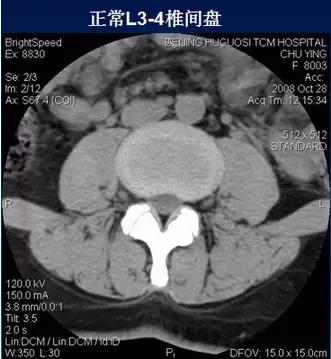

二、椎间盘膨出

椎间盘影均匀超出相应椎体边缘,轻度时CT表现为间盘后缘正常肾形凹陷消失,圆隆饱满。